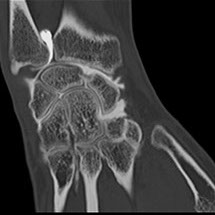

Cet examen consiste à injecter à l’aide d’une aiguille, sous guidage radiologique un produit de contraste iodé à l’intérieur d’une articulation. Les articulations concernées sont variées : genou, cheville, épaule, coude, poignet, hanche.

L’arthrographie est généralement immédiatement complétée par un scanner de l’articulation (arthroscanner). Ceci ne nécessitera pas de deuxième piqûre.

L’arthrographie, généralement couplée à l’arthroscanner permet au radiologue d’établir un diagnostic précis sur l’état des cartilages de l’articulation concernée, de déceler des ruptures partielles ou complètes des tendons, des ligaments, ou encore de déceler des corps étrangers au sein des articulations explorées. Cette exploration peut être couplée à une infiltration dans le même temps opératoire.